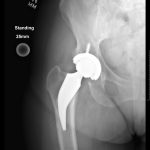

A 63-year-old Caucasian female weighing 244lbs diagnosed with osteo/degenerative arthritis received Advita’s Alteon Neck Preserving stem with a Bioloxdelta femoral head and InteGrip acetabular shell. The patient went under spinal anesthesia using a direct anterior surgical approach with an incision size of 9cm. There was an estimated blood loss of 200cc and surgery duration was 80 minutes. The patient was discharged after one day postoperative with a walker to in home care for rehabilitation.

Pre-Op AP Pelvis

Harris Hip Score 31 (max=100) | Oxford Hip Score 9 (max=48)

6-Week Post-Op

Harris Hip Score 68 (max=100) | Oxford Hip Score 38 (max=48)

3-Month Post-Op

Harris Hip Score 84 (max=100) | Oxford Hip Score 37 (max=48)

1-Year Post-Op

Harris Hip Score 100 (max=100) | Oxford Hip Score 46 (max=48)

CONCLUSION

Pre-op, this patient presented with low Harris Hip and Oxford Hip scores. The direct anterior approach used in her surgery has been associated with faster functional recover than the posterolateral approach, and one-year post-op, her scores increased by more than 69.0 percent on the Harris Hip and 80.4 percent on the Oxford Hip. The patient is satisfied with her total hip replacement, and her surgical outcomes continue to be followed on an annual basis. •